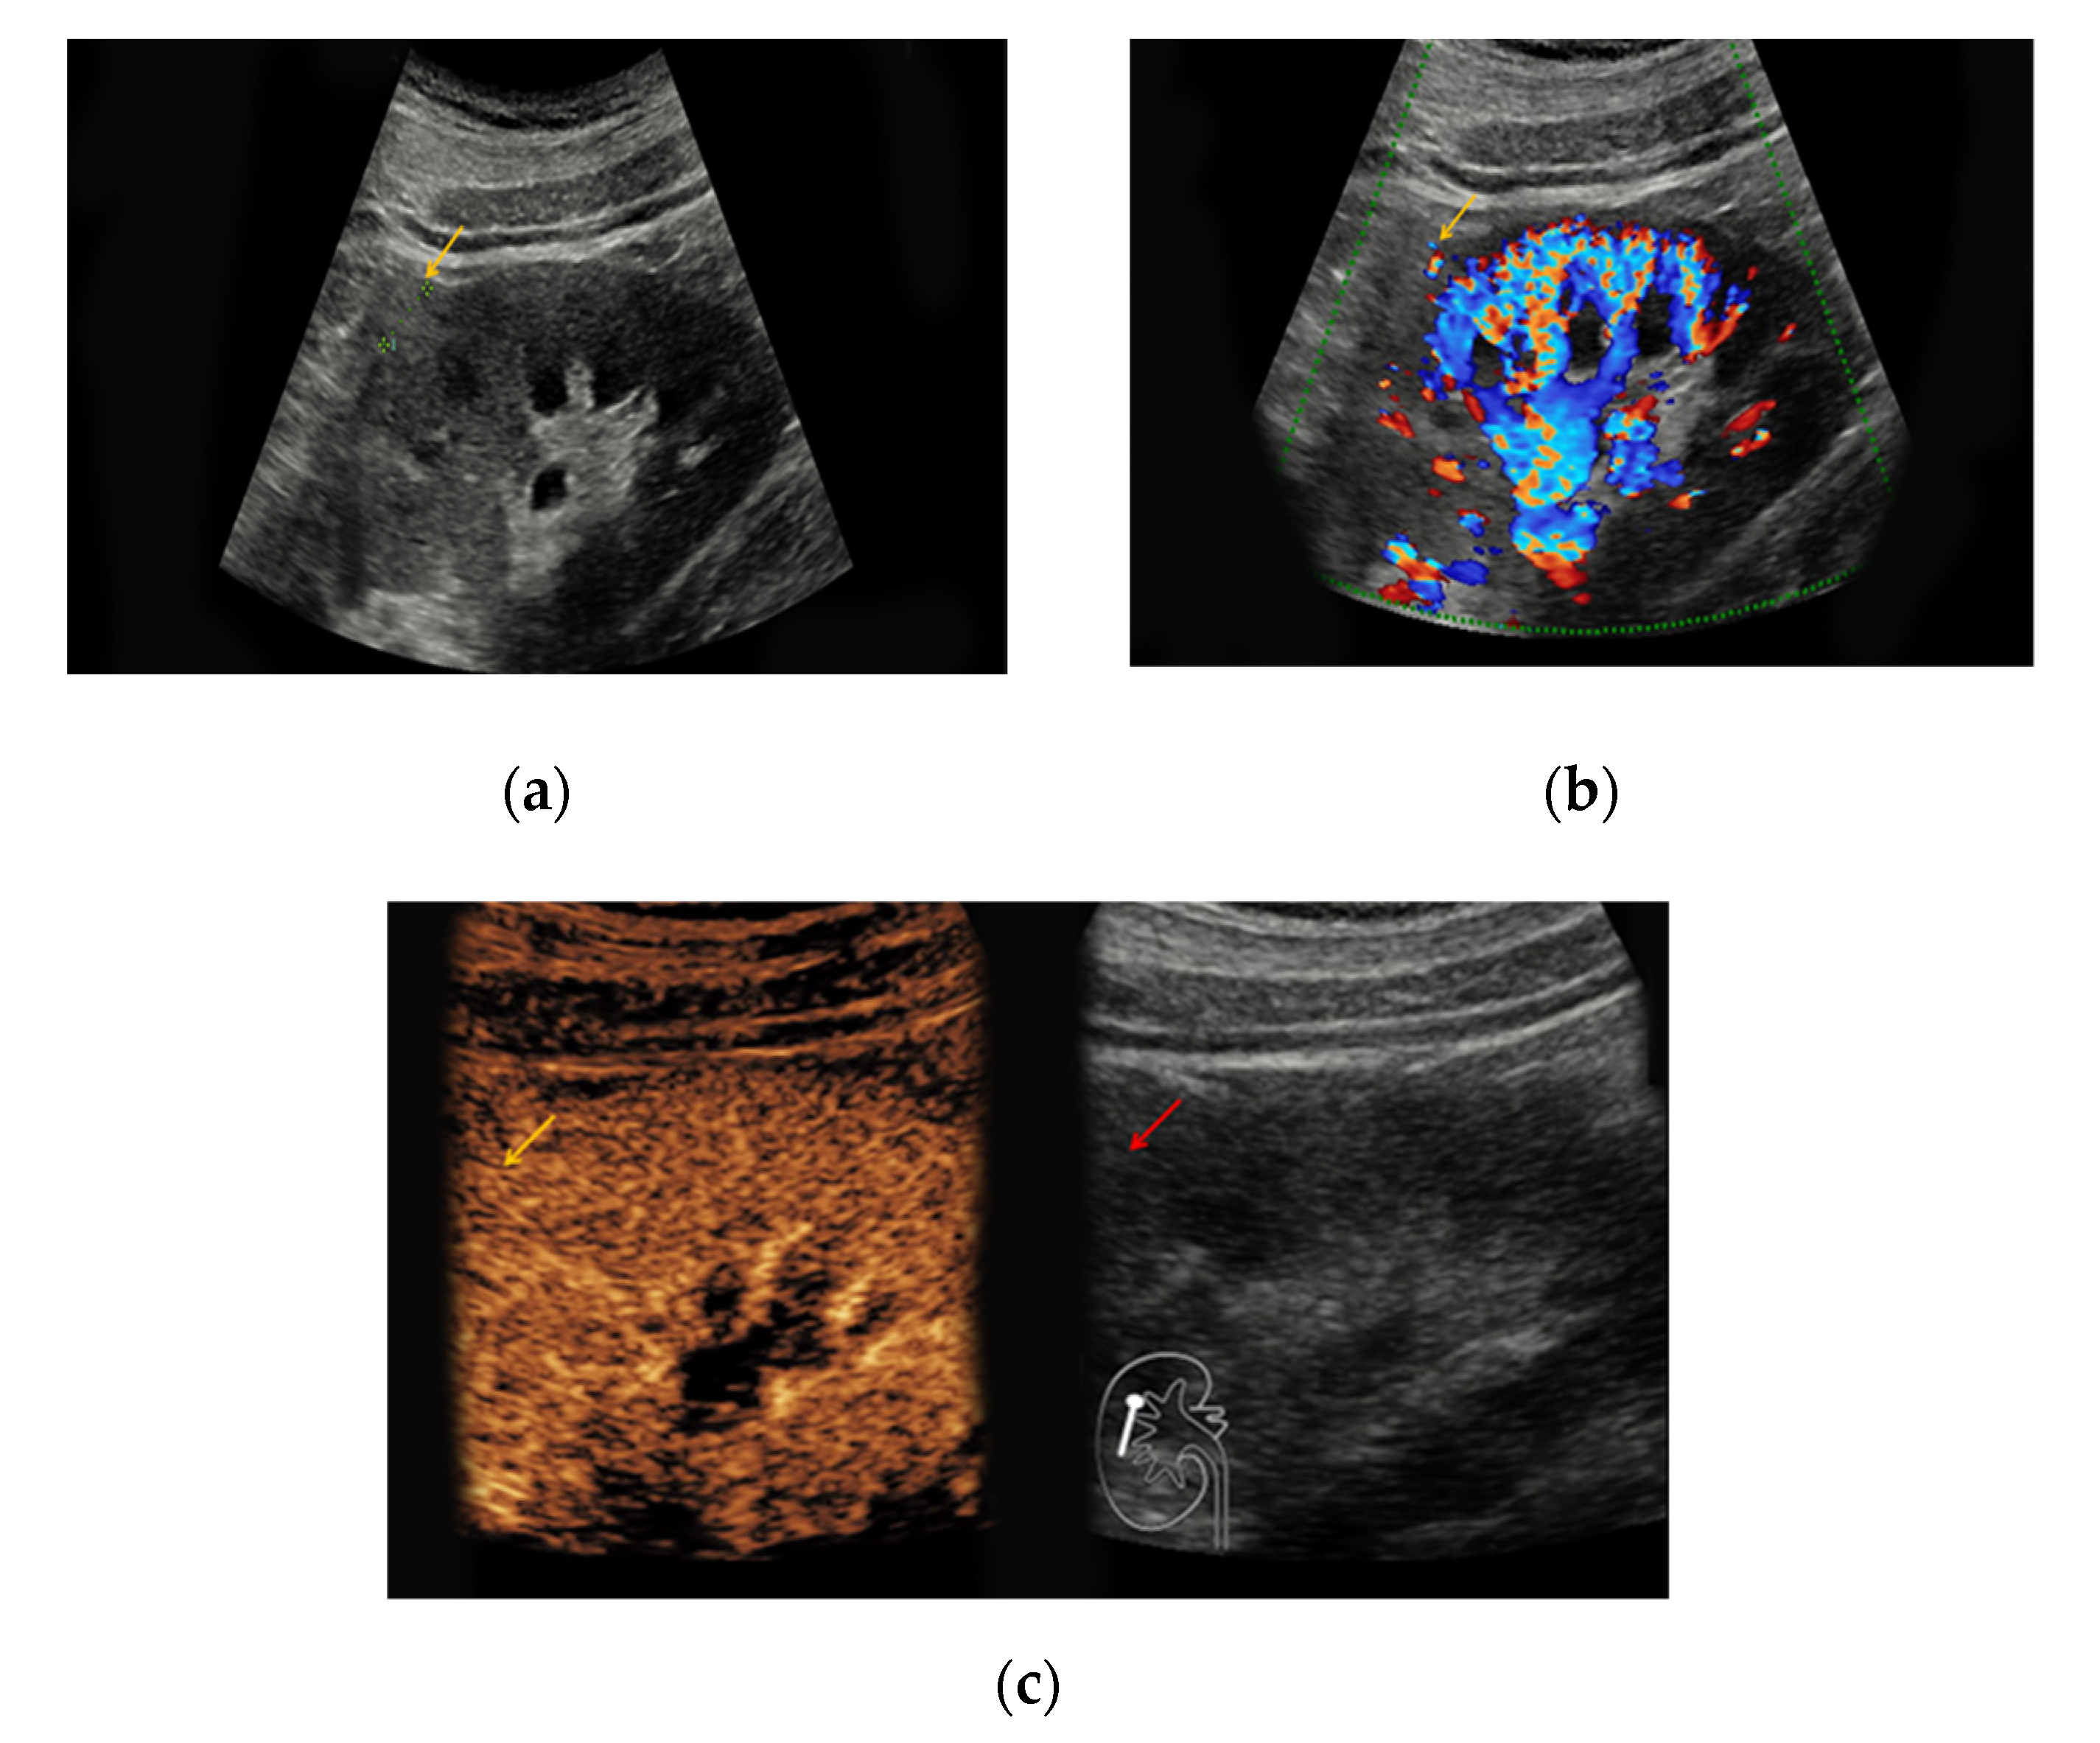

Figure 3. (a) Hyperechoic renal lesion with a diameter of 1.6 cm visualized in native B-mode (yellow arrow); (b) only slight vascularization was registered in Doppler mode (yellow arrow). (c,d) The lesion did not show hyperenhancement during the early (c, yellow arrow) and late phase (d, yellow arrow). Histopathological results showed a clear-cell renal cell carcinoma.

The heterogeneous sonomorphological features of the different histological subtypes of RCC are depicted in Supplementary Table S2. The majority of the CCRCC lesions presented as hypoechoic (33/47, 70%) compared to six hyperechoic lesions (13%) and five isoechoic lesions (11%). One lesion was iso-/hypoechoic (2%) and two lesions presented as hyper-/hypoechoic (4%). The PRCC lesions were hypoechoic in 27/42 cases (64%), hyperechoic in 8/42 cases (19%), and isoechoic in 5/42 cases (12%). One PRCC lesion could only be detected upon intravenous contrast application (2%) and one patient with bilateral PRCC presented with a hyperechoic lesion on the left and an isoechoic lesion on the right side (2%). Notably, 3/7 ChRCC lesions were hypoechoic (43%) compared to 4/7 isoechoic lesions (57%). Hypervascularization in Doppler Mode was detected in 7/47 CCRCC lesions (15%), in 2/42 PRCC lesions (5%), and 3/7 ChRCC lesions (43%). All 96 RCC lesions showed early enhancement upon application of contrast medium (Figure 3). Venous wash-out could be detected in 18/47 CCRCC lesions (38%), in 27/42 PRCC lesions (64%), and 6/7 ChRCC lesions (86%).